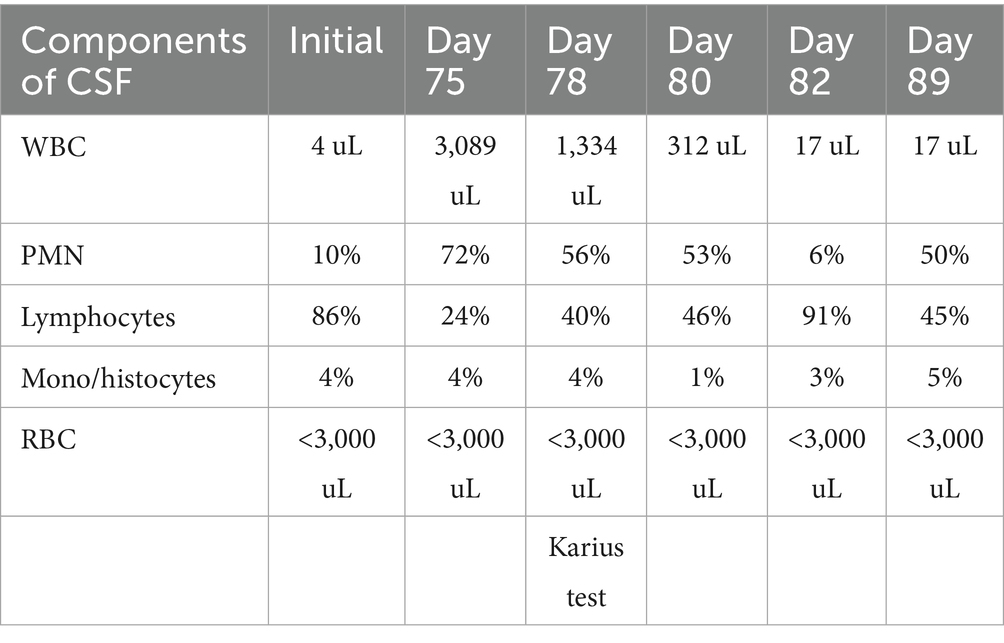

Furthermore, 6 weeks after his initial presentation, follow-up MRI revealed an increase in the size of the cavernous sinus lesion from 1.7 × 1.7 × 1.6 cm to 1.8 × 2.0 × 1.8 cm, demonstrating further extension of the lesion into the Meckel’s cave and along the trigeminal maxillary division, accompanied by further narrowing of the left ICA (Figure 1). He underwent a positron emission tomography (PET) scan to evaluate for other areas of malignancy/granulomatous disease, with the differential diagnoses being unchanged. The patient continued to experience headaches; however, cranial nerve III and VI palsies and diplopia had resolved.

Figure 1. MRI skull base T1 + C at 6-week follow-up with reported improvement of symptoms. (A) Interval increase in the cavernous sinus mass size with extension into the pituitary fossa. (B) Subtle enhancement along V2 on the left, suggesting infiltrative process(inlet). (C) Narrowing of the left ICA.